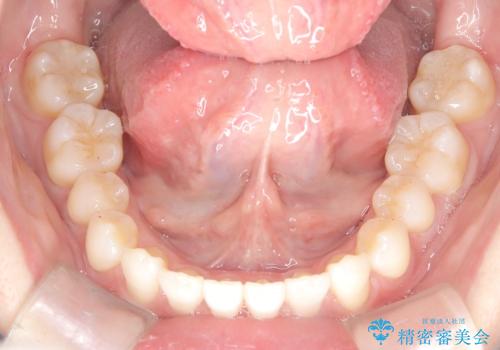

インビザラインモデレートによる前歯の叢生改善|IPR最小限で自然な歯並びへ

前歯の叢生は解消され、自然で調和の取れた歯並びが得られました。

「歯をほとんど削らずにきれいになった」と、患者様にもご満足いただけました。